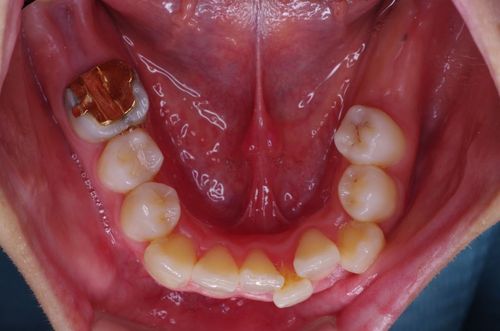

治療前

奥に2本のインプラントが入りました。